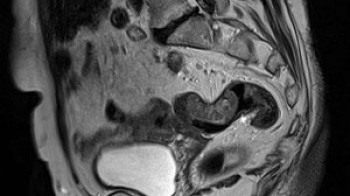

Šta su to MR enterografija i MR kolonografija-izvrsna skrining metoda pregled crijeva?

MR enterografija je pregled kojim se analiza tanko crijevo, a MR kolonografija je pregled debelog crijeva. Pregled tankog crijeva se obično koristi za praćenje ili otkrivanje upalnih i drugih bolesti tankog crijeva, a pregled debelog crijeva za brojne bolesti uključujući tumore debelog crijeva. Metoda je potpuno bezbolna, bez zračenja, sa izvrsnim prikazom zida probavne cijevi. Nema napuhivanja niti štetnog jonizujućeg zračenja kao kod CT pregleda crijeva. Za pregled , crijeva moraju biti očišćena-kao kod klasične kolonoskopije, a prije pregleda bilo tankog ili debelog , ćete dobiti oko 1,5l posebne tečnosti koju ćete popiti da bi se zid crijeva razdvojio I analiza bila bolja. Tečnost se pije oko 20-30min, nakon čega počinje pregled koji traje oko 20-30 minuta, uobičajeno je da se kontrastno sredstvo aplicira. –pregled tankog i debelog crijeva u jednom aktu - 500km.